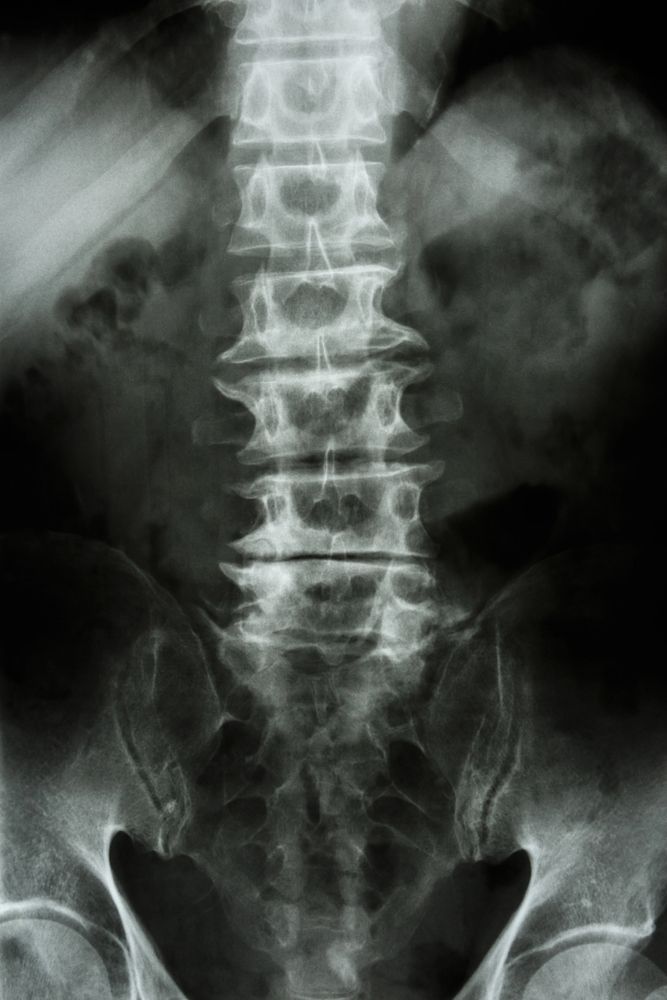

La radiografia standard è spesso il primo esame richiesto: mostra con chiarezza l'altezza dei dischi, la presenza di osteofiti, lo stato delle faccette articolari. La risonanza magnetica permette una valutazione più dettagliata dei dischi, dei nervi e dei tessuti molli, ed è indicata quando si sospetta un coinvolgimento radicolare significativo o quando i sintomi non rispondono al trattamento conservativo.

Un punto critico nella gestione clinica della spondiloartrosi è non far dipendere le decisioni terapeutiche esclusivamente dall'imaging. Come già anticipato, la correlazione tra gravità delle alterazioni radiografiche e intensità dei sintomi è spesso debole. Il trattamento si basa sulla persona e sul suo quadro funzionale, non sull'aspetto delle vertebre alla risonanza.